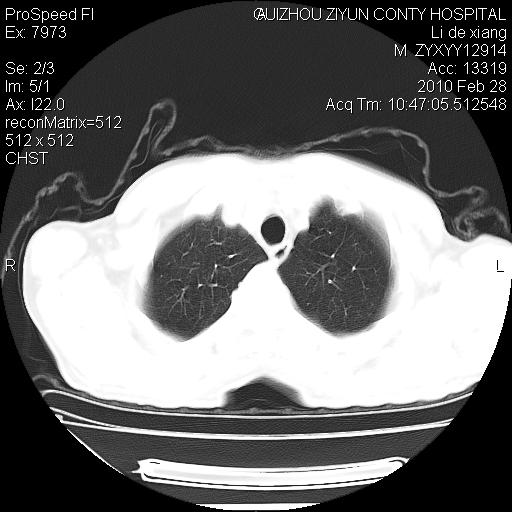

标题: CT24776:男 71Y 咳嗽咳痰胸痛两月,伴声音嘶哑。 [打印本页]

左侧中央型肺癌伴左肺上叶阻塞性肺炎及节段性不张可能性大,建议纤支镜检查!

左肺门部肿块,伴左上肺斑块影,周边模糊,支持左肺中央型肺癌伴节段性不张及阻塞性肺炎,结合支气管镜检查。

左上叶支气管狭窄,阻塞性病变,肺门肿块,纵隔及肺门淋巴结增大,中央性肺癌